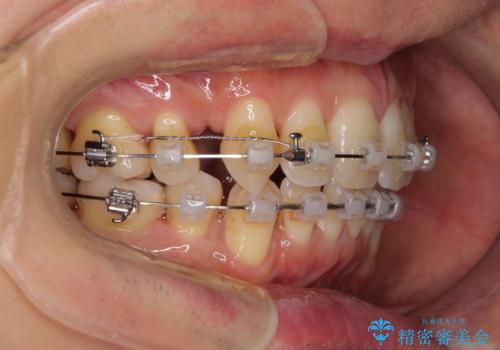

- クリアブラケット

- 口元の閉じにくさと、前歯のでこぼこの歯並びを気にして来院された患者様です。

口元を積極的に引っ込めるために、上下左右の小臼歯計4本を抜歯することとしました。

叢生が強い場合、抜歯スペースが叢生を解消するために消費されるため、口元の突出感があまり改善されないことがあります。

今回の治療では、奥歯が前方に傾斜した歯並びだったため、奥に起き上がることで歯列が後方に移動し、横側からも口元が引っ込んだ感じが分かるほど改善されました。